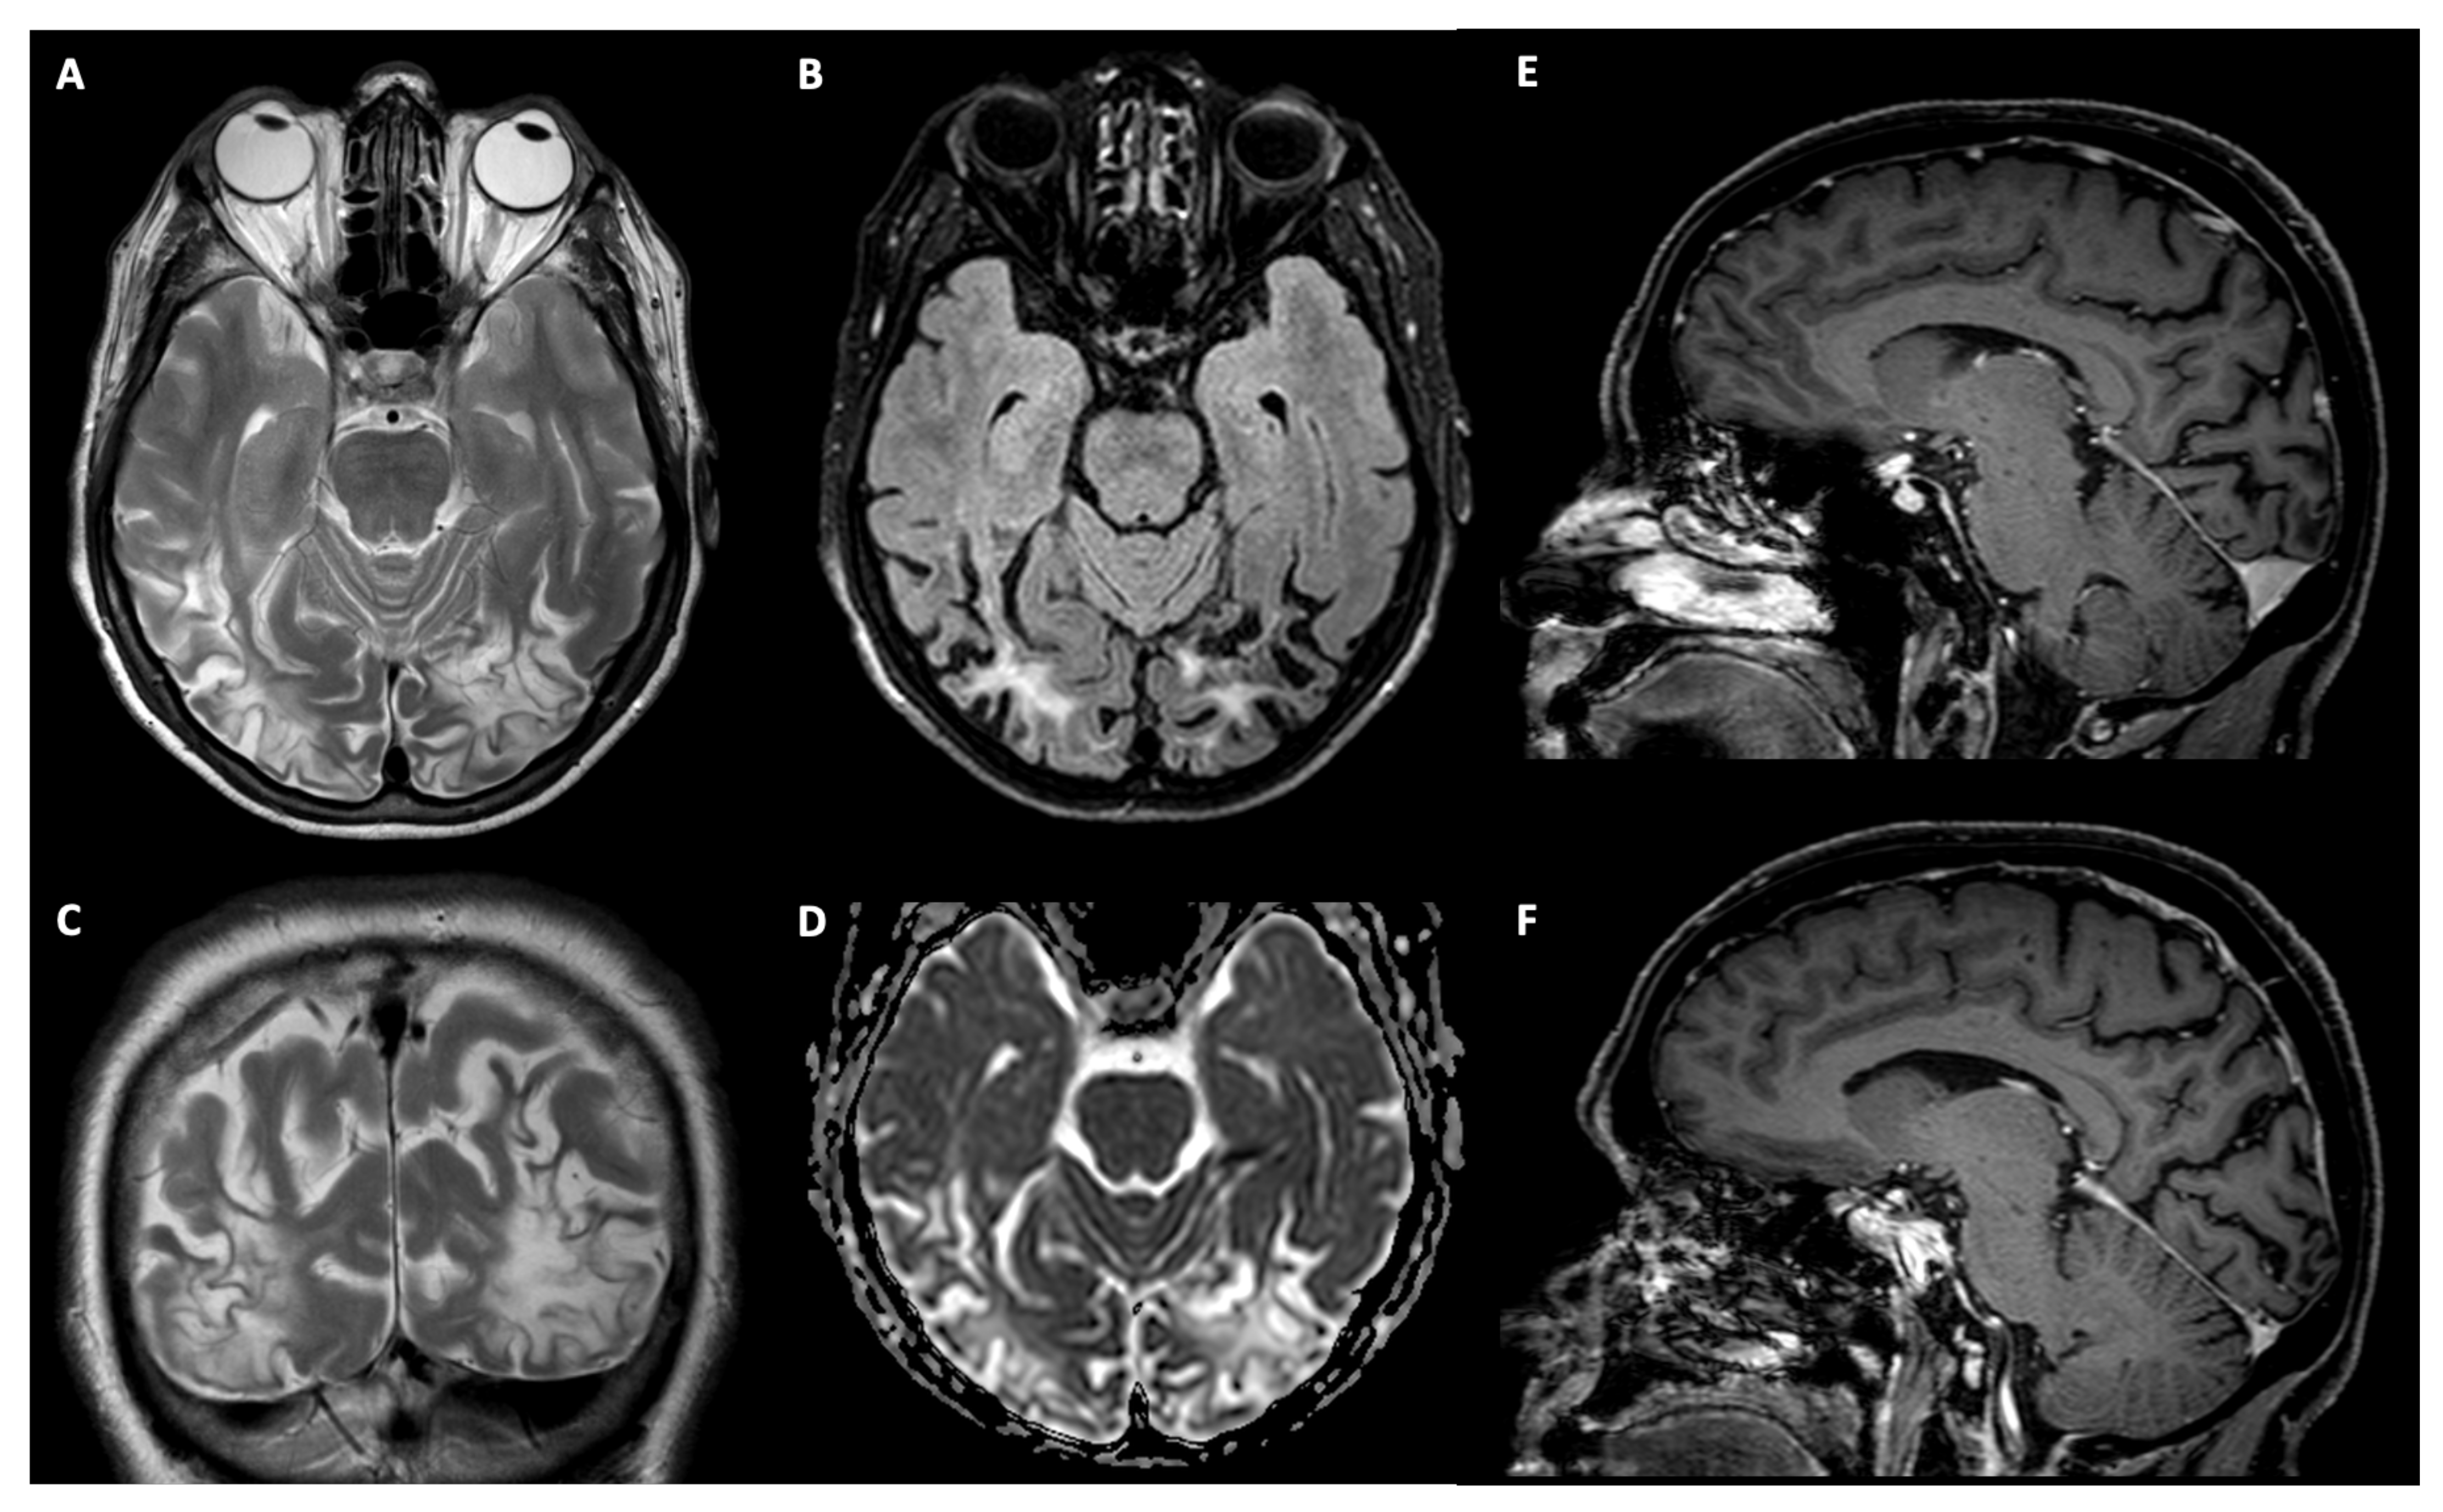

2.1.1. Patient TMA